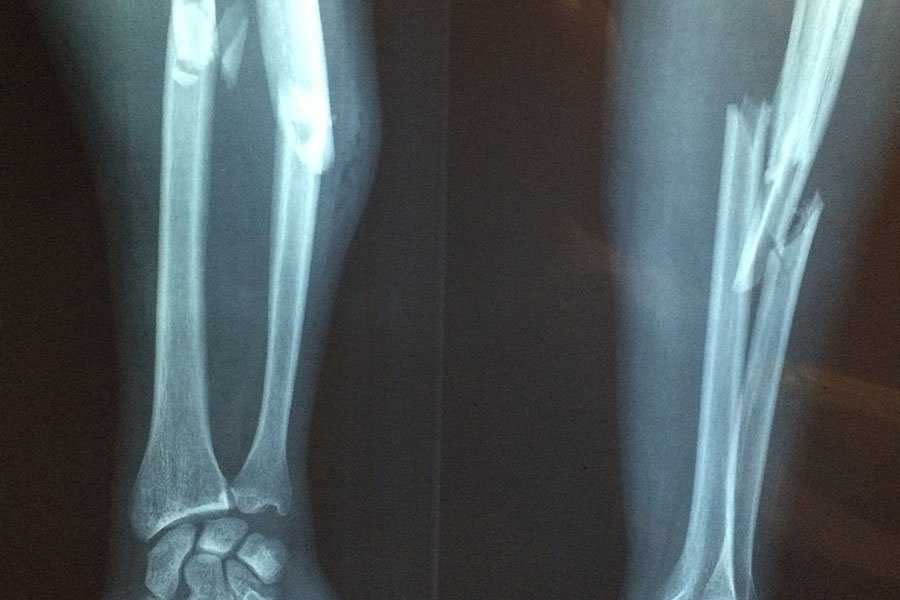

Фото из открытых источников